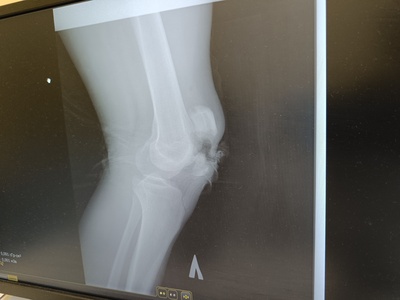

Похожая была история ) только открытый перелом )

Иллюстрация к комментарию